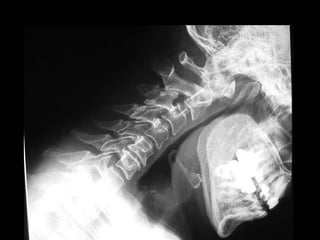

CERVICAL EM PERFIL Posição do Paciente:  Ortostática, com os braços para traz e com as mãos dadas forçando os ombros para baixo; Alinhar a linha médio coronal com a LCE, estenda levemente o queixo para a frente (a fim de evitar a sobreposição da região cervical superior pela mandíbula); Raio Central:  Perpendicular horizontal, incidindo ao nível de C4; Filme:  18x24 em longitudinal, borda superior do chassi 3cm acima do meato acústico externo; DFF:  de 150 cm.

CERVICAL EM PERFIL

Posi ç ão do Paciente:   A posi ç ão ereta  é  preferida (sentado ou em p é ), mas a radiografia pode ser feita na posi ç ão deitada se a condi ç ão do paciente assim o exigir; Alinhe o plano coronal m é dio ao RC e  à  linha m é dia da mesa ou do porta-filme. Levante o bra ç o e o ombro do paciente pr ó ximos do filme, flexionando o coto ­ velo e deixando o antebra ç o apoiado na cabe ç a.   Posicione o bra ç o e o ombro distantes do filme para baixo e ligeiramente anteriores a fim de situar a cabe ç a umeral anteriormente  à s v é rtebras. Mantenha o t ó rax e a cabe ç a na posi ç ão mais lateral verdadeira poss í vel; Raio Central:  P erpendicular ao filme. RC centralizado em T1; DFF:  De 100 cm POSIÇÃO CERVICO TORÁCICO DO NADADOR (C4 – T7)

POSIÇÃO CERVICO TORÁCICO DO NADADOR (C4 – T7)